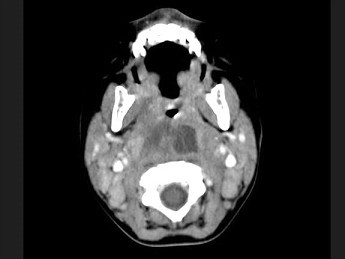

[多选题] 10个月大的婴儿,发热,曾患中耳炎,CT扫描如图所示,请选择正确的描述或诊断()A . 咽后壁软组织肿胀B . 其内密度不均C . 颈椎骨质未见明显异常D . 考虑为咽后壁脓肿E . 考虑为咽后壁寒性脓肿

[多选题] 10个月大的婴儿,发热,曾患中耳炎,CT扫描如图所示,请选择正确的描述或诊断()A .咽后壁软组织肿胀B .其内密度不均C .颈椎骨质未见明显异常D .考虑为咽后壁脓肿E .考虑为咽后壁寒性脓肿